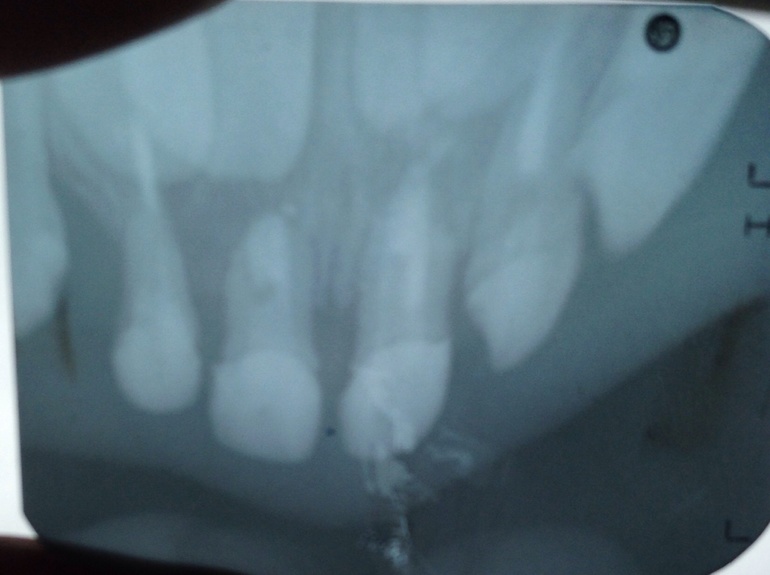

Здравствуйте, Алина Владимировна!

Напомню, что ребенок сильно ударился передними зубами, единицами. Шатаются сильно ( до этого уже шатались немного)

Рентген на окне и лампе, не знаю, как лучше